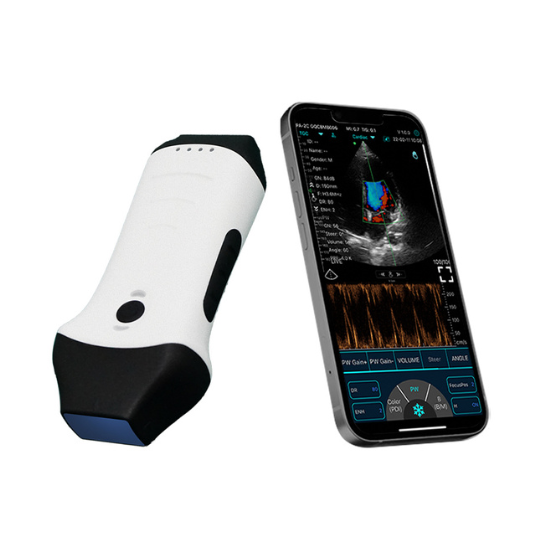

3-in-1 Color Doppler Scanner

Powerful 3-in-1 Color Doppler Scanner – Linear, Convex & Cardiac Imaging in One Portable Device!

This is a state-of-the-art, handheld ultrasound device featuring a dual-probe design - convex, linear with cardiac functions, making it ideal for full-body diagnostics. Compatible with smartphones, iPads, and PCs, it offers both wired and wireless connectivity for maximum flexibility. With an IP68 waterproof rating, the scanner allows you to perform scans anytime, anywhere, with confidence and convenience.

- Low cost and no monthly subscription fees

- Fast free delivery + 7 days return if unsatisfied

- Compatible with Windows, Android and iOS platforms

- Can be used with tablets, smartphones and computers

- Lightweight, pocket-size, easy to carry and easy to use

- It is Wireless and can connect via in-built Wifi system

- Portable - you can scan anybody, anytime and anywhere

- 18 months warranty & can be extended up to 3 years

- Free Software & Free lifetime software upgrade

- FDA, CE and UKCA Certified